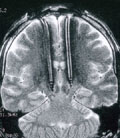

Θεσσαλονίκη: Το ένα τρίτο του πληθυσμού της γης είναι μολυσμένο με το μυκοβακτηρίδιο της φυματίωσης. Υπολογίζεται ότι κάθε χρόνο εμφανίζονται 20 εκατομμύρια ασθενείς από τους οποίους 9 εκατ. είναι νέα περιστατικά και 2 εκατ. άνθρωποι πεθαίνουν κάθε χρόνο από την ασθένεια αυτή.